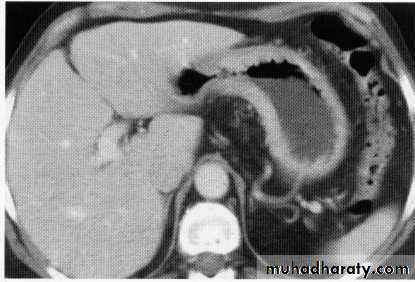

hepatic mets

hepatic mets,arterial phase

hepatic mets venous phase